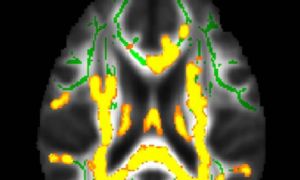

Mỡ bụng cảnh báo bệnh Alzheimer?

Theo nghiên cứu mới đây, việc có mỡ bụng ở tuổi trung niên có liên quan đến sự phát triển của bệnh Alzheimer.